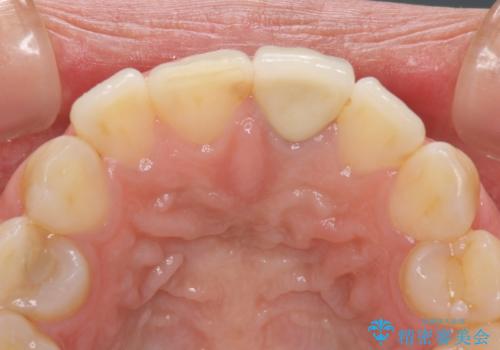

- 前歯をメタルの被せものにしており、セラミックに変えるのを希望された患者様です。

土台も金属だったため、歯がかなり黒く変色していました。

色は完全にとるのが不可能であることをご了承頂いた上で、土台と被せものの治療を行いました。

今回は歯自体が黒くなって歯茎から透けて見えている黒ずみのため、セラミック治療で改善させることは困難だというお話をしました。その上でできる範囲できれいに治療することになりました。

今回のように歯自体が金属イオンで黒く変色すると、被せものをメタルフリーにしても黒ずみをすべて隠すのは困難になります。一方、被せものの金属が見えていることが原因の黒ずみの場合は、セラミック治療できれいになりますので、気になる方は一度ご来院ください。